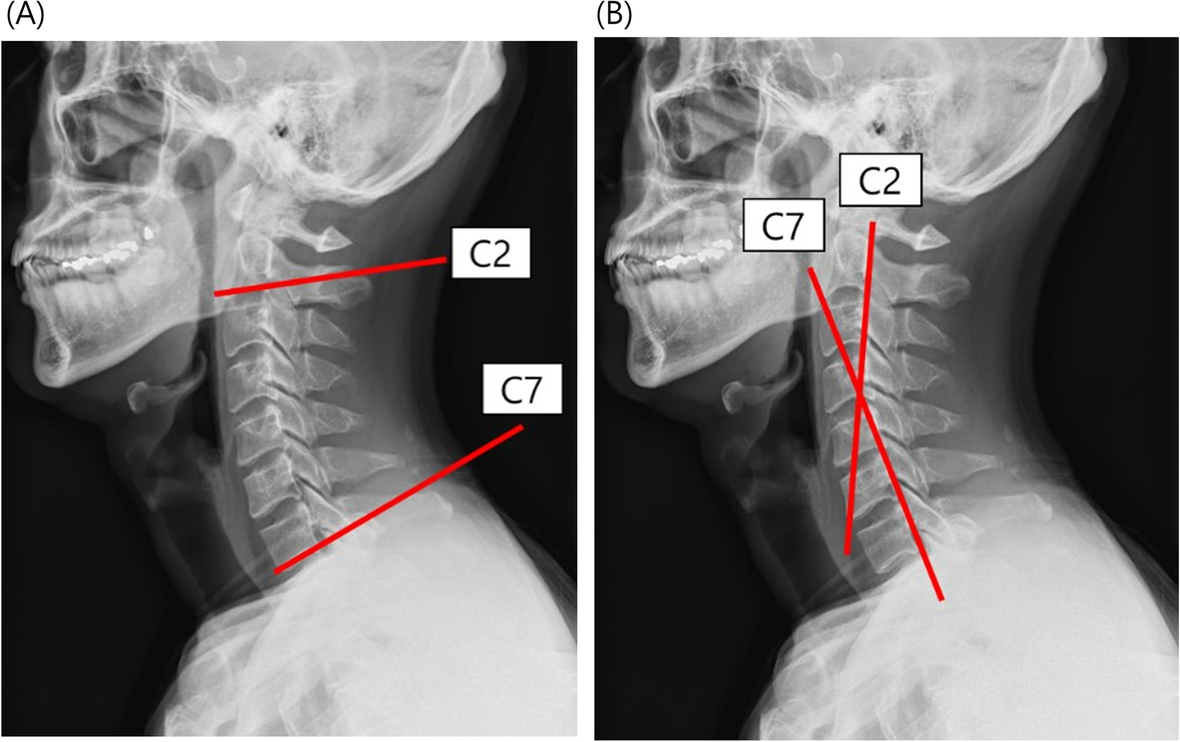

Severe Lordosis

Lordosis (Swayback): Types, Causes & Symptoms Lumbar lordosis or hyperlordosis - Back Care Clinic Lordosis: Guide To Causes, Symptoms, And Treatments What Is Lordosis? Lumbar Lordosis: Definition, Causes, Symptoms, Diagnosis, and ... Severe Lordosis